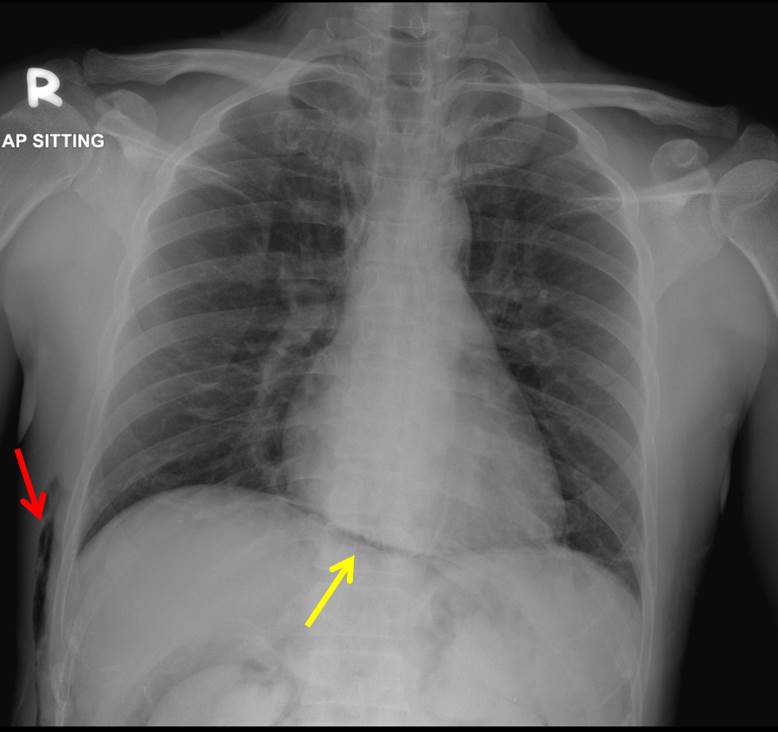

Chest xray PA view showing gas under right diaphragm. Download

Chest xray PA view showing gas under right diaphragm. Download Gas Under Diaphragm Sign Name The stomach bubble forms a round/ovoid shape under the left hemidiaphragm. Features that suggest chilaiditi sign include: Pneumoperitoneum (aeroperitoneum is a rare synonym 12) describes gas within the peritoneal cavity, often due to critical illness. Haustra within the gas suggesting that it is within the. Gas between liver and diaphragm. As the stomach has a thick wall, there is a. Gas Under Diaphragm Sign Name.